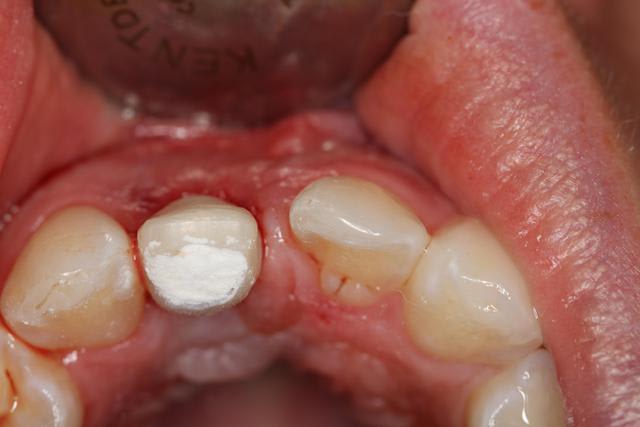

Implant posé ce matin

Le guide n'a pas été utilisé. Pas assez stable, délicat pour la visibilité, me sentais moins bien avec que sans : l'axe me paraissait pas correspondre, peur de fraiser de la résine.

Extraction simple, hauteur racine 10mm.

Alvéole propre, "boulevard" pour implanter.

Premier forage légerement en palatin, trop car petite excursion dans canal retro incisif.

Reprise de l'axe finalement au fond de l'alvéole.

Implant Legacy (ayé) 3 4,2x16mm

Bonne stabilité primaire, saignement abondant.

Utilisation pilier provisoire résine plateforme 4.7, injection de flow et polissage pour galber mais pas trop pour que la gencive revienne.

Pas de sutures, pas besoin.